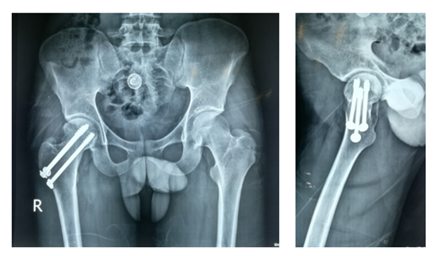

After selecting a case according to inclusion and exclusion criteria, patients were evaluated preoperatively. An elaborate history was taken. This was followed by a general examination and local examination. After admission, patients were put on surface traction to the affected limb with 1/10th of the patient's body weight. All patients underwent preoperative counselling regarding the operative procedure, probable complications, outcome, and other treatment options, along with their merits and demerits. After being informed, written consent was obtained. After preparing the patients for operation, Closed reduction is performed with the patient in the supine position on a fracture table (Figure 1). Reduction was confirmed by C-arm. After reduction, three guide wires are placed, usually in an inverted triangular fashion (Figure 2).

The screw lengths are measured, and drilling is performed using a 4.5 mm cannulated reamer. The screws are then inserted (for the BDSF technique, a specific sequence of middle, then superior, and lastly inferior screw insertion is to be followed). All three screws are inserted less than 5 mm subchondrally (Figure 3,4). In all cases, a prophylactic antibiotic was given. In the postoperative ward, proper fluid and hemodynamic balance were ensured. Change of posture was done twice an hour. The antibiotic was continued for 3 days. Analgesics were given to ensure a pain-free postoperative period. On the first postoperative day, patients were allowed to sit on the side of the bed. Patients were being educated about breathing exercises, isometric quadriceps exercises, gluteal exercises, and ankle pumping exercises. An immediate postoperative X-ray was done (Figure 5). After checking the dressing, on 4th POD, they were discharged from the hospital if their postoperative period was uneventful. Oral antibiotics were given for 10 days. Advice was given to continue isometric quadriceps exercise. Regarding ambulation, they were advised to do non-weight-bearing (of the affected side) crutch ambulation until directed by the physician. Use of elevated toilet seats onwards is also advised. The next follow-up would be given at the 14th POD. The first follow-up was given at 14th POD to check any signs of infection, pain status, and distal neurovascular status. The stitch was removed on the same day. Advice given about isometric quadriceps exercise, active abduction, extension exercise, and stretching exercise of the hip joint. The next follow-up was the 6th week after the operation. The range of motion was tested. An X-ray was done to check callus formation. Improvements were noted. Partial weight bearing was given at this follow-up. Subsequent follow-up was given at 12 weeks and every 4 weeks until union has been achieved or at least 9 months (Figures 6-10).